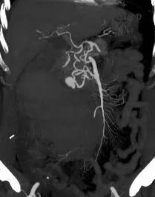

紧急的增强CT检查结果,证实了我们的最坏猜想:肠系膜上动脉的一个分支上,有一个动脉瘤破裂了! 血液正从破口不断涌入腹腔。

精准导航:在DSA透视的引导下,我们像“巡航导弹”一样,将一根细长而柔软的导管,从股动脉一路精准地“行驶”到肠系膜上动脉,最终抵达破裂的动脉瘤分支。

封堵“决堤口”:通过导管,我们向破裂的动脉瘤及其两端释放了数枚微小的 “弹簧圈” 。这些弹簧圈会迅速在破口处盘绕成团,形成一个致密的“塞子”,瞬间堵死破口,让血液无法再流出。

手术成功了! 屏幕上显示,破裂的血管不再造影剂外溢。这意味着,“决堤口”被成功封堵。整个过程,患者体表只有一个针眼大小的伤口。术后,王先生的血压很快稳定下来,脱离了生命危险。